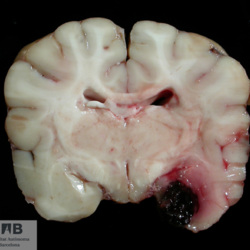

Pàgina anterior de 637 Pàgina següent 3181 total Canine Specie: Canine Organ: Nerve Lesion: - Lesion modifier: - Disease: - Files/Expedient: N-214/09 Not viewed Canine Specie: Canine Organ: Brain Lesion: Hemorrhage Lesion modifier: - Disease: - Files/Expedient: N-190/09 Not viewed Feline Specie: Feline Organ: Lung Lesion: Atelectasis Lesion modifier: - Disease: - Files/Expedient: N-167/09 Position: 136 (2 views) Canine Specie: Canine Organ: Pituitary gland Lesion: Carcinoma Lesion modifier: Carcinoma - Adenocarcinoma Disease: - Files/Expedient: N-113/09 Not viewed Canine Specie: Canine Organ: Pituitary gland Lesion: Carcinoma Lesion modifier: Carcinoma - Adenocarcinoma Disease: - Files/Expedient: N-113/09 Not viewed Pàgina anterior de 637 Pàgina següent Títol Select...Avian (Exotic) (110)Avian (Poultry) (76)Bovine (317)Canine (935)Caprine (47)Equine (257)Feline (326)Ferret (19)General (127)Marine mammal (22)Non-human primate (20)Ovine (328)Porcine (379)Rabbit (61)Reptile (38)Rodent (28)Wildlife (91) Format Select...- (60)Abomasum (37)Adrenal gland (10)Blood (7)Blood vessel (50)Body as a whole (19)Bone (57)Bone marrow (21)Brain (93)Cloaca (1)Diaphragm (2)Ear (5)Esophagus (39)Eye (16)Fetus (12)Gallbladder (23)Gizzard (2)Heart (265)Intestine (356)Joint (32)Kidney (443)Larynx (5)Liver (326)Lung (264)Lymph node (91)Mammary gland (10)Mediastinum (1)Muscle (22)Nasal cavity (22)Nerve (7)Omasum (5)Oral cavity (63)Ovary (14)Oviduct (8)Pancreas (7)Parathyroid (5)Penis (10)Peritoneum (65)Pharynx (9)Pituitary gland (6)Placenta (7)Prostate (8)Proventriculus (3)Reticulum (1)Rumen (28)Sinus (7)Skin (181)Spinal cord (15)Spleen (105)Stomach (125)Teeth (1)Testicle (11)Thoracic cavity (31)Thymus (13)Thyroid gland (5)Tongue (32)Tonsils (11)Trachea (11)Urethra (5)Urinay bladder (61)Uterus (27)Vagina (1)Vulva (1)Yolk sac (1) Cobertura Select...- (152)Abomasitis (26)Abscess (27)Acidosis (1)Adenocarcinoma (20)Adenoma (9)Aerosacculitis (6)Agenesis (1)Agnathia (1)Alopecia (7)Amyloidosis (12)Aneurysm (6)Angiectasis (1)Anthracosis (1)Arteritis (11)Arthritis (15)Arthrogryposis (6)Artifact (4)Ascites (13)Atelectasis (8)Atherosclerosis (5)Atresia (1)Atrial septal defect (2)Atrophy (10)Autolysis (7)Bronchitis (6)Bronchopneumonia (26)Cachexia (2)Carcinoma (103)Cardiomyopathy (19)Cellulitis (2)Chemodectoma (4)Cholangiohepatitis (4)Cholangitis (19)Cholecystitis (4)Cholestasis (5)Chondrodysplasia (2)Chondrosarcoma (2)Chronic passive congestion (13)Chylothorax (2)Cirrhosis (6)Coelomitis (3)Coenurus cerebralis (4)Colitis (40)Congestion (17)Conjunctivitis (5)Coronitis (3)Cryptorchidism (3)Cyst (25)Cystitis (24)Dermatitis (69)Diaphragmatic hernia (4)Dilation (28)Discospondylitis (1)Disseminated intravascular coagulation (7)Dyschondroplasia (1)Dysplasia (29)Ectopia cordis (1)Ectopic ureter (1)Edema (55)Emphysema (5)Encephalitis (5)Endocardiosis (14)Endocarditis (26)Endometritis (5)Enteritis (118)Enterolith (6)Epulis (3)Esophagitis (14)Fasciitis (1)Fibrosis (7)Fibrous osteodystrophy (8)Fistula (1)Folliculitis (3)Fracture (2)Gastritis (34)Gingivitis (5)Glioma (8)Glomerulonephritis (21)Glossitis (25)Glycogenosis (1)Gout (8)Granuloma (2)Granulosa cell tumor (4)Hemangioma (9)Hemangiosarcoma (46)Hematoma (8)Hemoglobinuria (2)Hemopericardium (12)Hemoperitoneum (2)Hemorrhage (100)Hemosiderosis (7)Hemothorax (2)Hepatitis (78)Hernia (11)Histiocytosis (3)Hydatid cyst (11)Hydrocephalus (9)Hydrometra (1)Hydronephrosis (22)Hydropericardium (6)Hydrothorax (3)Hydroureter (5)Hyperkeratosis (8)Hyperostosis (4)Hyperplasia (37)Hypertrophy (9)Hypopigmentation (1)Hypoplasia (7)Hypopyon (1)Impaction (6)Infarction (63)Insulinoma (6)Intussusception (5)Jaundice (17)Laminitis (2)Laryngitis (2)Leiomyoma (5)Leukemia (13)Lipidosis (36)Lipoma (7)Lymphadenitis (45)Lymphadenopathy (7)Lymphangiectasia (6)Lymphangitis (5)Lymphoma (221)Malacia (11)Malignant melanoma (15)Mast cell tumor (11)Mastitis (8)Megaesophagus (2)Melanosis (3)Melena (4)Meningioma (6)Meningitis (6)Meningocele (2)Meningoencephalitis (5)Mesothelioma (5)Methemoglobinemia (2)Mineralization (10)Mucocele (5)Mucometra (1)Multilobular bone tumor (1)Mummification (3)Myelofibrosis (1)Myocarditis (4)Myositis (5)Necrosis (81)Nephritis (113)Nephroblastoma (6)Nephrosclerosis (1)Nephrosis (14)Neuritis (1)Obstruction (13)Omasitis (4)Omphalitis (1)Omphalophlebitis (7)Orchitis (4)Osteoarthrosis (5)Osteomyelitis (9)Otitis (2)Palatoschisis (3)Pancreatitis (3)Panniculitis (3)Papilloma (7)Parakeratosis (14)Patent ductus arteriosus (6)Peliosis hepatis (1)Perforation (17)Pericarditis (35)Peritonitis (39)Persistent right aortic arch (1)Pharyngitis (2)Pheochromocytoma (2)Phlebitis (2)Placentitis (6)Pleuritis (21)Pleuropneumonia (24)Pneumonia (109)Pneumothorax (3)Polycystosis (14)Polyp (5)Polyserositis (6)Posthitis (1)Proctitis (4)Prolapse (3)Prostatitis (3)Proventriculitis (1)Pyelonephritis (24)Pyometra (6)Pyothorax (4)Rhinitis (11)Rumenitis (6)Rupture (24)Salpingitis (3)Sarcoma (57)Sclerosis (1)Scoliosis (2)Seminoma (2)Sequestrum (2)Serous atrophy (14)Sinusitis (7)Splenitis (14)Splenomegaly (9)Spondylitis (6)Spondylosis (1)Stenosis (9)Stomatitis (32)Tenosynovitis (2)Teratoma (3)Thricobezoar (2)Thrombosis (16)Tonsilitis (4)Torsion (13)Tracheitis (4)Tympany (7)Typhlitis (8)Typhlocolitis (4)Ulcer (43)Urethritis (1)Urolithiasis (36)Uroperitoneum (1)Uveitis (1)Vasculitis (15)Ventricular septal defect (3)Volvulus (11) Matèria Select... - (14)- (1653)- (152)Abomasitis - Catarrhal (2)Abomasitis - Catarrhal-hemorrhagic (1)Abomasitis - Chronic (1)Abomasitis - Fibrinous-necrotizing (2)Abomasitis - Hyperplasic (5)Abomasitis - Hyperplasic - Chronic (1)Abomasitis - Necrotic (1)Abomasitis - Necrotizing (2)Abomasitis - Ulcerative (5)Adenocarcinoma (9)Aerosacculitis - Granulomatous (1)Amyloidosis - Chronic (1)Arteritis - Necrotic (2)Arteritis - Necrotizing (1)Arthritis - Chronic (4)Arthritis - Fibrinous-purulent (3)Arthritis - Serous (4)Arthritis - Subacute (1)Ascites - Serous (1)Atrophy - Serous (1)Bronchitis - Catarrhal (3)Bronchitis - Suppurative (1)Bronchopneumonia - Catarrhal-purulent (17)Bronchopneumonia - Fibrinous (1)Bronchopneumonia - Granulomatous (1)Bronchopneumonia - Purulent (1)Bronchopneumonia - Suppurative (5)Carcinoma - Adenocarcinoma (33)Carcinoma - Adenocarcinoma - Hepatocellular (2)Carcinoma - Adenocarcinoma - Mucinous (1)Carcinoma - Basosquamous (1)Carcinoma - Cholangiocellular (3)Carcinoma - Hepatocellular (4)Carcinoma - Metastatic (3)Carcinoma - Squamous cell carcinoma (13)Carcinoma - Transitional cell (2)Cardiomyopathy - Dilated (13)Cardiomyopathy - Hypertrophic (6)Cellulitis - Necrotizing (1)Cholangitis - Chronic (8)Cholangitis - Hyperplasic (3)Cholecystitis - Fibrinous-necrotizing (1)Coelomitis - Fibrinous (1)Coelomitis - Granulomatous (1)Colitis - Catarrhal (3)Colitis - Catarrhal-hemorrhagic (1)Colitis - Fibrinous (1)Colitis - Fibrinous-necrotizing (1)Colitis - Fibrinous-necrotizing (Diphtheritic) (6)Colitis - Granulomatous (2)Colitis - Hemorrhagic (4)Colitis - Hemorrhagic-necrotizing (3)Colitis - Necrotizing (2)Colitis - Ulcerative (6)Congestion - Chronic (2)Conjunctivitis - Hyperplasic (1)Conjunctivitis - Purulent (3)Coronitis - Ulcerative (1)Cystitis - Chronic (3)Cystitis - Fibrinous (1)Cystitis - Fibrinous-necrotizing (1)Cystitis - Follicular (1)Cystitis - Hemorrhagic (6)Cystitis - Hemorrhagic-ulcerative (1)Cystitis - Necrotizing (9)Cystitis - Perforated (1)Dermatitis - Granulomatous (14)Dermatitis - Hyperkeratotic (10)Dermatitis - Hyperplasic (proliferative) (1)Dermatitis - Hyperplastic (10)Dermatitis - Necrotizing (4)Dermatitis - Pustular (4)Dermatitis - Ulcerative (2)Dilation - Chronic (1)Discospondylitis - Necrotizing (1)Dysplasia - Follicular (5)Edema - Interstitial (6)Emphysema - Interstitial (1)Encephalitis - Granulomatous (1)Encephalitis - Nonsuppurative (1)Endocardiosis - Mitral (7)Endocardiosis - Mitral - Chronic (5)Endocarditis - Valvular (6)Endocarditis - Valvular - Mitral (7)Endocarditis - Valvular - Pulmonic (1)Endocarditis - Valvular - Subacute (1)Endocarditis - Valvular - Subaortic (5)Endocarditis - Valvular - Tricuspid (4)Endometritis - Purulent (3)Endometritis - Purulent-hemorrhagic (2)Enteritis - Catarrhal (23)Enteritis - Catarrhal - Acute (1)Enteritis - Catarrhal-hemorrhagic (5)Enteritis - Catarrhal-hemorrhagic - Acute (2)Enteritis - Fibrinous (16)Enteritis - Fibrinous - Acute (3)Enteritis - Fibrinous-necrotizing (7)Enteritis - Granulomatous (14)Enteritis - Granulomatous - Chronic (1)Enteritis - Granulomatous - Multifocal (1)Enteritis - Hemorrhagic (17)Enteritis - Hemorrhagic - Acute (1)Enteritis - Hemorrhagic-necrotizing (1)Enteritis - Hyperplasic (proliferative) (4)Enteritis - Necrotizing (4)Enteritis - Necrotizing - Acute (1)Enteritis - Necrotizing - Hemorrhagic (1)Enteritis - Necrotizing-ulcerative (2)Enteritis - Ulcerative (1)Enteritis - Ulcerative-hemorrhagic (1)Esophagitis - Erosive-ulcerative (6)Esophagitis - Necrotizing (4)Esophagitis - Ulcerative (1)Esophagitis - Ulcerative-necrotizing (1)Fasciitis - Fibrinous-purulent (1)Folliculitis - Purulent (2)Gastritis - Catarrhal (2)Gastritis - Chronic (1)Gastritis - Follicular (1)Gastritis - Hemorrhagic (2)Gastritis - Hemorrhagic-necrotizing (1)Gastritis - Hypertrophic (2)Gastritis - Inclusion bodies (1)Gastritis - Mineralization (1)Gastritis - Mycotic (1)Gastritis - Necrotizing (2)Gastritis - Ulcerative (6)Gastritis - Uremic (3)Gingivitis - Erosive (2)Gingivitis - Hyperplasic (proliferative) (1)Gingivitis - Necrotizing (1)Glomerulonephritis - Chronic (7)Glomerulonephritis - Membranoproliferative (3)Glomerulonephritis - Membranoproliferative - Chronic (1)Glomerulonephritis - Membranous (3)Glomerulonephritis - Membranous - Chronic (1)Glomerulonephritis - Proliferative (2)Glomerulonephritis - Subacute (1)Glossitis - Erosive (2)Glossitis - Granulomatous (6)Glossitis - Hyperplasic (1)Glossitis - Hyperplasic (proliferative) (2)Glossitis - Hyperplastic (1)Glossitis - Necrotizing (2)Glossitis - Necrotizing - Focal (1)Glossitis - Ulcerative (6)Glossitis - Ulcerative - Multifocal (1)Glossitis - Ulcerative - Subacute (1)Glycogenosis (1)Granuloma - Eosinophilic (1)Hemangiosarcoma - Metastatic (2)Hemorrhage - Acute (1)Hemorrhage - Subcapsular (3)Hepatitis - Abscess (9)Hepatitis - Acute (3)Hepatitis - Chronic (4)Hepatitis - Chronic interstitial (6)Hepatitis - Granulomatous (7)Hepatitis - Interstitial - Multifocal (1)Hepatitis - Interstitial - Subacute (1)Hepatitis - Necrotizing (17)Hepatitis - Necrotizing - Acute (2)Hepatitis - Necrotizing - Hemorrhagic (1)Hepatitis - Necrotizing - Subacute (1)Hepatitis - Pyogranulomatous (7)Hepatitis - Subacute (4)Hydronephrosis - Chronic (1)Hydropericardium - Chronic (1)Hyperplasia - Erythroid (1)Hyperplasia - Lymphoid (3)Hyperplasia - Myeloid (1)Hyperplasia - Nodular (8)Hypertrophy - Concentric (2)Hypertrophy - Eccentric (3)Infarction - Acute (17)Infarction - Acute - Multifocal (2)Infarction - Chronic (5)Infarction - Chronic - Multifocal (1)Infarction - Subacute (18)Infarction - Subacute - Focal (2)Laminitis - Chronic (2)Laryngitis - Necrotic (1)Laryngitis - Necrotizing (1)Leukemia - Lymphoid leukemia (2)Leukemia - Non-lymphoid leukemia (6)Lipidosis - Multifocal (1)Lipidosis - Panlobular (1)Lipidosis - Panlobular - Generalized (2)Lymphadenitis - Granulomatous (24)Lymphadenitis - Granulomatous - Chronic (3)Lymphadenitis - Hemorrhagic (1)Lymphadenitis - Necrotizing (5)Lymphadenitis - Necrotizing (caseous) (11)Lymphangitis - Granulomatous (1)Lymphangitis - Purulent (1)Lymphangitis - Ulcerative (1)Lymphoma - Alimentary lymphoma (7)Lymphoma - Cutaneous lymphoma (6)Lymphoma - Lymphosarcoma (2)Lymphoma - Mediastinal lymphoma (1)Lymphoma - Multicentric lymphoma (29)Malignant melanoma - Malignant (1)Malignant melanoma - Metastatic (1)Mast cell tumor - Metastatic (1)Mastitis - Fibrinous-purulent (2)Mastitis - Necrotic (1)Mastitis - Purulent (3)Mastitis - Suppurative (1)Meningitis - Fibrinous-purulent (2)Meningitis - Purulent (4)Meningoencephalitis - Necrotizing (3)Meningoencephalitis - Nonsuppurative (2)Mineralization - Metastatic (4)Myocarditis - Fibrous - Chronic (1)Myocarditis - Granulomatous (1)Myositis - Purulent (2)Necrosis - Acute (1)Necrosis - Cortical (5)Necrosis - Follicular (1)Necrosis - Papillary (8)Necrosis - Papillary - Acute (3)Necrosis - Subacute (3)Necrosis - Tubular (6)Nephritis - Embolic (2)Nephritis - Embolic suppurative (7)Nephritis - Granulomatous (27)Nephritis - Granulomatous - Chronic (1)Nephritis - Granulomatous - Multifocal (1)Nephritis - Interstitial (6)Nephritis - Interstitial - Acute (4)Nephritis - Interstitial - Chronic (41)Nephritis - Interstitial - Subacute (12)Nephritis - Purulent (7)Nephritis - Purulent - Acute (2)Nephritis - Purulent - Multifocal (3)Nephrosis - Cholemic (3)Nephrosis - Hemoglobinuric (10)Omasitis - Fibrinous-necrotizing (1)Omasitis - Hyperkeratotic (1)Omasitis - Necrotizing (2)Omphalophlebitis - Fibrinous-purulent (2)Omphalophlebitis - Purulent (3)Orchitis - Necrotizing (1)Osteomyelitis - Necrotizing (7)Osteomyelitis - Purulent (2)Otitis - Necrotizing (1)Otitis - Proliferative (1)Pancreatitis - Acute (1)Pancreatitis - Chronic (1)Pancreatitis - Granulomatous (1)Panniculitis - Fibrinous-purulent (1)Panniculitis - Necrotic (1)Panniculitis - Parasitic (1)Perforation - Acute (2)Pericarditis - Fibrinous (19)Pericarditis - Fibrinous - Subacute (1)Pericarditis - Fibrinous-necrotizing (1)Pericarditis - Fibrinous-purulent (3)Pericarditis - Fibrous (1)Pericarditis - Fibrous - Chronic (1)Pericarditis - Gangrenous (6)Pericarditis - Granulomatous (1)Pericarditis - Granulomatous - Chronic (2)Peritonitis - Acute (1)Peritonitis - Fibrinous (11)Peritonitis - Fibrinous - Subacute (1)Peritonitis - Fibrinous-purulent (5)Peritonitis - Fibrous (3)Peritonitis - Granulomatous (6)Peritonitis - Purulent (1)Peritonitis - Purulent-hemorrhagic (1)Peritonitis - Pyogranulomatous (3)Pharyngitis - Fibrinous-necrotizing (1)Pharyngitis - Ulcerative (1)Pheochromocytoma - Metastatic (1)Phlebitis - Purulent (1)Placentitis - Fibrinous-necrotizing (1)Placentitis - Necrotic (1)Placentitis - Necrotizing (1)Pleuritis - Chronic (1)Pleuritis - Fibrinous (3)Pleuritis - Fibrinous-purulent (2)Pleuritis - Fibrous (2)Pleuritis - Granulomatous (3)Pleuritis - Hyperplastic (2)Pleuritis - Purulent (2)Pleuritis - Pyogranulomatous (1)Pleuropneumonia - Fibrinous (13)Pleuropneumonia - Fibrinous-necrotizing (5)Pleuropneumonia - Granulomatous (2)Pleuropneumonia - Hemorrhagic-necrotizing (4)Pneumonia - Aspiration (11)Pneumonia - Bronchointerstitial (4)Pneumonia - Bronchointerstitial - Subacute (1)Pneumonia - Embolic (5)Pneumonia - Granulomatous (37)Pneumonia - Granulomatous - Multifocal (4)Pneumonia - Hemorrhagic-necrotizing (2)Pneumonia - Interstitial (7)Pneumonia - Interstitial - Acute (8)Pneumonia - Interstitial - Chronic (6)Pneumonia - Interstitial - Subacute (15)Pneumonia - Necrotizing (2)Pneumonia - Pyogranulomatous (2)Pneumonia - Verminous (5)Polyserositis - Fibrinous (6)Polyserositis - Fibrous (1)Proctitis - Fibrinous-necrotizing (1)Proctitis - Parasitic (2)Prostatitis - Purulent (1)Pyelonephritis - Acute (2)Pyelonephritis - Chronic (3)Rhinitis - Catarrhal (2)Rhinitis - Fibrinous (1)Rhinitis - Granulomatous (4)Rhinitis - Purulent (3)Rumenitis - Acute (1)Rumenitis - Erosive (1)Rumenitis - Necrotizing (1)Rupture - Acute (3)Sarcoma - Fibrosarcoma (12)Sarcoma - Hemangiosarcoma (11)Sarcoma - Histiocytic (7)Sarcoma - Metastatic (1)Sarcoma - Multilobular tumor of bone (1)Sequestrum - Chronic (2)Sinusitis - Suppurative (1)Splenitis - Granulomatous (8)Splenitis - Granulomatous - Chronic (1)Splenitis - Necrotizing (3)Splenitis - Necrotizing (caseous) (2)Spondylitis - Necrotizing (2)Stenosis - Intestinal (1)Stenosis - Valvular - Subaortic (4)Stomatitis - Erosive (12)Stomatitis - Erosive-ulcerative (3)Stomatitis - Fibrinous-necrotizing (1)Stomatitis - Fibrinous-necrotizing (Diphtheritic) (1)Stomatitis - Granulomatous (1)Stomatitis - Hyperplasic (1)Stomatitis - Hyperplasic (proliferative) (1)Stomatitis - Necrotizing (2)Stomatitis - Ulcerative (5)Stomatitis - Ulcerative - Multifocal (1)Stomatitis - Ulcerative-necrotizing (1)Tonsilitis - Necrotizing (4)Torsion - Acute passive hyperemia (5)Tracheitis - Catarrhal (3)Tracheitis - Fibrinous (1)Tracheitis - Granulomatous (1)Typhlitis - Catarrhal (1)Typhlitis - Fibrinous-necrotizing (2)Typhlitis - Hemorrhagic (2)Typhlitis - Ulcerative-hemorrhagic (1)Typhlocolitis - Fibrinous-necrotizing (2)Typhlocolitis - Proliferative (1)Ulcer - Chronic (6)Ulcer - Multifocal (2)Ulcer - Mycotic (1)Ulcer - Perforated (6)Urethritis - Hemorrhagic (1)Urolithiasis - Chronic (2)Uveitis - Granulomatous (1)Vasculitis - Granulomatous (1)Vasculitis - Necrotizing (1) Editor Select...- (1970)Acidosis (2)Actinobacillosis (Pleuropneumonia) (11)Aelurostrongylosis (2)African horse sickness (13)African swine fever (14)Alopecia X (1)Anaplasmosis (4)Anthrax (2)Aortic thromboembolism (feline) (7)Ascariasis (15)Aspergillosis (18)Atopic dermatitis (1)Atrophic rhinitis (3)Babesiosis (6)Blackhead (1)Bluetongue (11)Border disease (2)Bovine viral diarrhea (21)Brucellosis (2)Candidiasis (5)Canine distemper (14)Caprine arthritis-encephalitis (2)Capture myopathy (1)Cardiac insufficiency (17)Caseous lymphadenitis (7)Chlamydiosis (2)Classical swine fever (19)Clostridiosis (19)Coccidiosis (9)Coenurosis (4)Colibacillosis (21)Contagious ecthyma (7)Copper toxicosis (11)Cowdriosis (Heartwater) (3)Cryptococcosis (3)Cryptosporidiosis (2)Cysticercosis (23)Demodicosis (1)Diabetes (1)Dicrocoeliosis (5)Dictyocaulosis (4)Dirofilariasis (7)Discoid lupus erythematosus (3)Echinococcosis (17)Edema disease (7)Egg drop syndrome (1)Encephalitozoonosis (5)Enterotoxemia (1)Enzootic bovine leukosis (46)Epitheliogenesis imperfecta (3)Equine rhinopneumonitis (2)Equine verminous arteritis (strongylosis) (7)Erysipelas (5)Exudative epidermitis (7)Fasciolasis (11)Feline eosinophilic dermatoses (1)Feline hepatic lipidosis (8)Feline histiocytosis (4)Feline infectious peritonitis (38)Feline leukemia (4)Feline lower urinary tract disease (3)Feline panleukopenia (16)Feline viral rhinotracheitis (1)Flea allergy dermatitis (1)Foot and mouth disease (2)Gasterophilosis (4)Glasser's disease (15)Gousiekte (4)Gout (6)Haemonchosis (9)Hemolytic anemia (4)Hemorrhagic diathesis (1)Hepatic insufficiency (11)Hepatosis dietetica (7)Herpesvirosis (6)Hyperadrenocorticism (7)Hyperparathyroidism (10)Hypertrophic osteopathy (6)Hypervitaminosis D (1)Hypodermosis (1)Inclusion body hepatitis (4)Infectious bovine rhinotracheitis (5)Infectious bronchitis (5)Infectious canine hepatitis (13)Influenza (4)Juvenile nephropathy (8)Lamb dysentery (4)Leishmaniasis (28)Leptospirosis (1)Leukosis (5)Listeriosis (4)Lumpy skin disease (3)Maedi-visna (4)Malignant catarrhal fever (12)Mange (6)Mannheimiosis (5)Marek's disease (7)Metabolic bone disease (2)Mucoid enteropathy (5)Mulberry heart disease (5)Myasis (1)Mycobacteriosis (22)Mycosis fungoides (6)Myxomatosis (3)Necrobacillosis (5)Neonatal isoerythrolysis (6)Nocardiosis (4)Oestrosis (2)Onchocerciasis (1)Osteochondrosis (1)Ostertagiosis (6)Ovine pulmonary adenocarcinoma (5)Oxyuriasis (1)Pacheco's disease (4)Papillomatosis (6)Paratuberculosis (18)Parvovirosis (17)Pasteurellosis (11)Pemphigus foliaceus (1)Periodontal disease (1)Polioencephalomalacia of ruminants (4)Polyarteritis nodosa (3)Polycystic kidney disease (13)Porcine circovirosis (11)Porcine dermatitis and nephropathy syndrome (9)Porcine proliferative enteropathy (4)Porcine reproductive and respiratory syndrome (6)Porcine stress syndrome (1)Pox (13)Pregnancy toxemia (3)Proventricular dilatation disease (2)Pseudotuberculosis (yersiniosis) (2)Psittacine beak and feather disease (PBFD) (5)Pyoderma (4)Q fever (4)Rabbit hemorrhagic disease (2)Renal insufficiency (12)Reticuloendotheliosis (2)Rhodococcosis (1)Rickets (1)Rinderpest (2)Salmonellosis (34)Sarcosporidiosis (2)Schmallenberg (7)Septicemia (23)Spirocercosis (11)Streptococcosis (5)Strongylosis (1)Swine dysentery (5)Systemic coronavirosis (5)Tetralogy of Fallot (5)Theileriosis (13)Thromboembolism (5)Toxoplasmosis (11)Transmissible viral proventriculitis (1)Traumatic reticuloperitonitis (3)Traumatism (16)Tuberculosis (58)Ulcerative lymphangitis (1)Uremic syndrome (20)Viral arthritis (6)White muscle disease (9)Wobbler syndrome (2)Xanthomatosis (1)Zygomycosis (4) Idioma Select...- (1180)Bacterial (501)Degeneration (106)Fungal (46)Hemodynamic (112)Idiopathic (22)Inflammation (58)Malformation (88)Neoplasia (343)Nutritional (41)Parasitic (243)Physical/Chemical (93)Toxic (44)Viral (304) Ítem destacat Avian (Poultry) Broilers. Livers are swollen, pale, friable with petechial or echymotic hemorrhages. Adenovirus (group I).